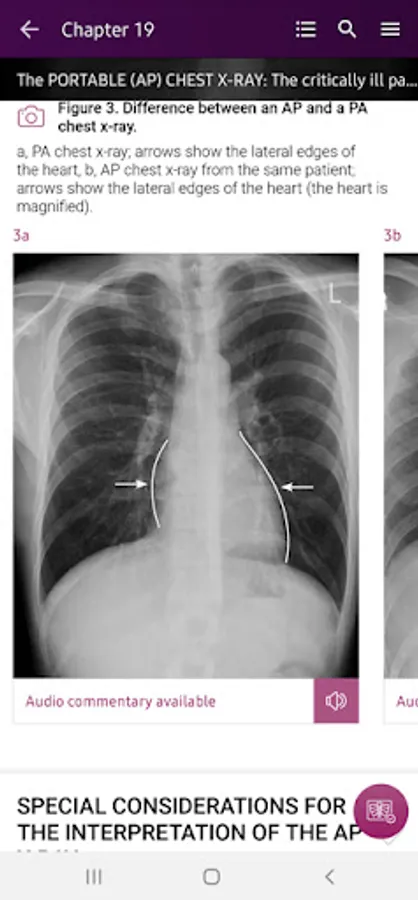

Section II* introduces the concept of radiological zones to give you a starting point in the understanding of the radiological anatomy of the chest. The next chapters review in detail the radiological anatomy of specific anatomical structures, also provide examples of how the x-ray image can change due to pathology. The final chapter explains how the individual structures come together to form the radiological image.